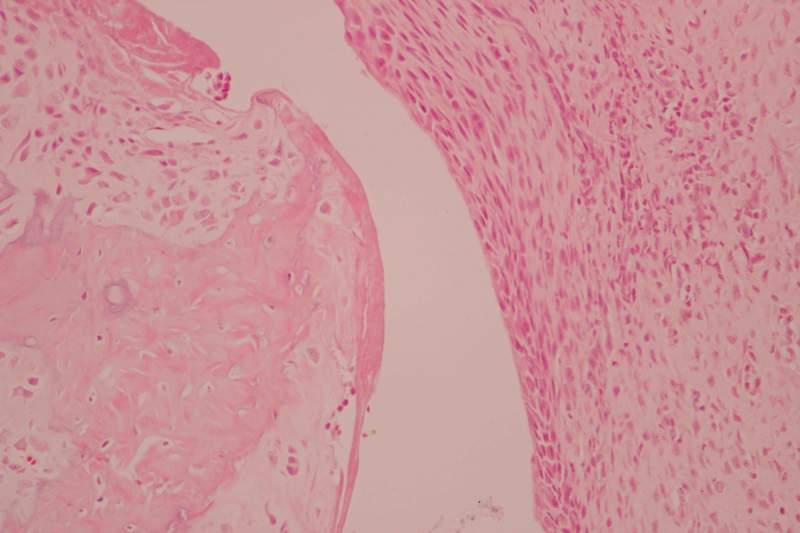

求助一组病理读片,CIA大鼠踝关节滑膜 已有1人参与